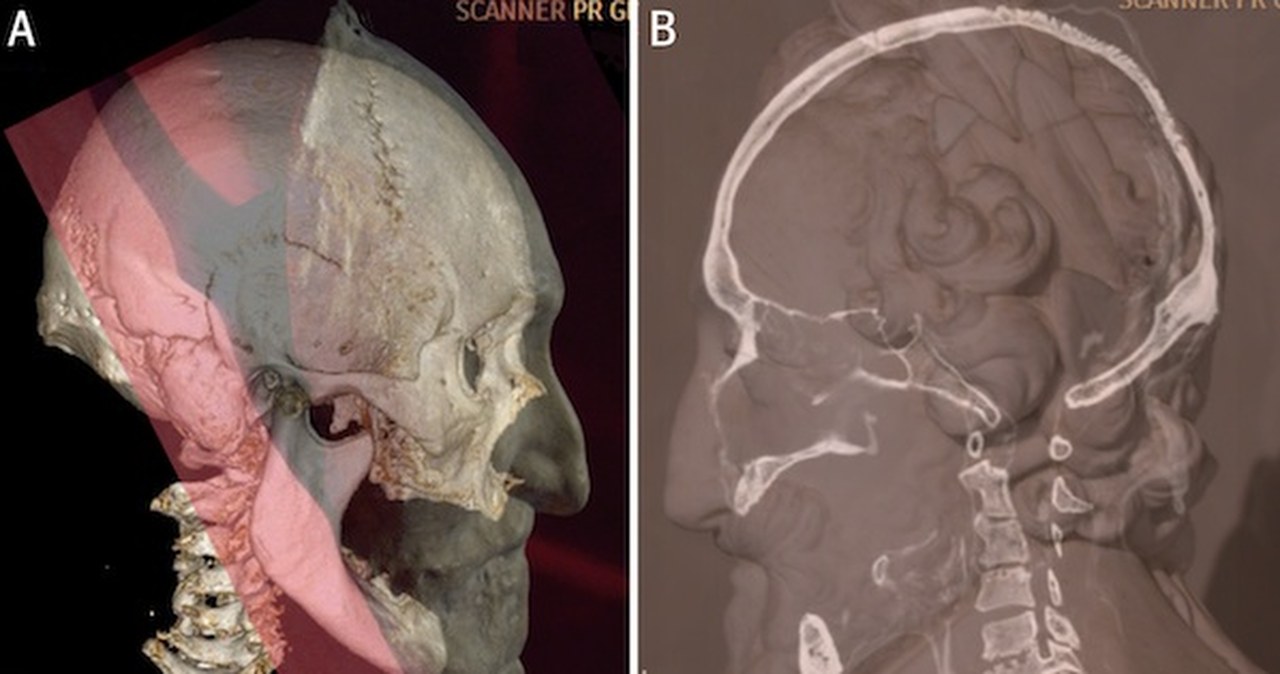

Szef ekipy lekarzy patologów i genetyków ze szpitala uniwersyteckiego w Garches pod Paryżem, 34-letni Philippe Charlier, ustalił, że w - "bezpańska" głowa należała do Henryka iv Burbona m.in. dzięki analizie jego włosów i brody oraz uszkodzeniom czaszki, które - jego zdaniem - są pozostałością po nieudanym zamachu na życie tego króla. W czasie wielkiej rewolucji francuskiej głowa została odcięta od zabalsamowanych zwłok władcy, które znajdowały się w królewskiej bazylice w Saint-Denis.